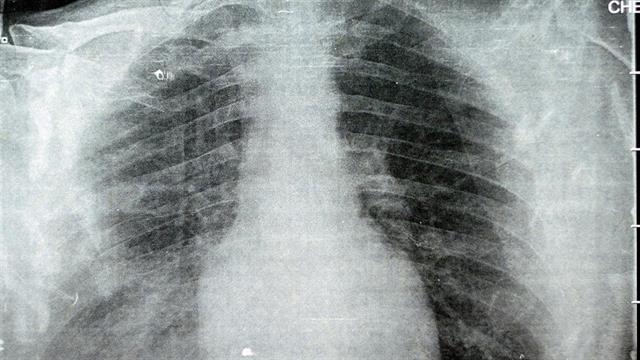

Τις αιτίες εμφάνισης κρουσμάτων πνευμονίας από μυκόπλασμα (Mycoplasma pneumoniae), εξηγούν επιστήμονες σε άρθρο που δημοσιεύτηκε πρόσφατα στο επιστημονικό περιοδικό The Lancet.

Όπως αναφέρουν, το Mycoplasma pneumoniae είναι μια κοινή αιτία λοιμώξεων της αναπνευστικής οδού με την πνευμομία της κοινότητας. Σε σύγκριση με άλλα παθογόνα, το μυκόπλασμα είναι άτυπο από πολλές απόψεις: είναι ένας από τους μικρότερους αυτοαναπαραγόμενους οργανισμούς, έχει μειωμένο και εξαιρετικά σταθερό γονιδίωμα (0,8 Mbp), στερείται κυτταρικού τοιχώματος, αναπτύσσεται αργά (χρόνος δημιουργίας 6 ώρες ), απαιτεί στενή επαφή για μετάδοση και έχει μια ξεχωριστή εμφάνιση ασθένειας (άτυπη πνευμονία), η παθογένεση της οποίας μπορεί να περιλαμβάνει ανοσία που προκαλείται από το κύτταρο ξενιστή.